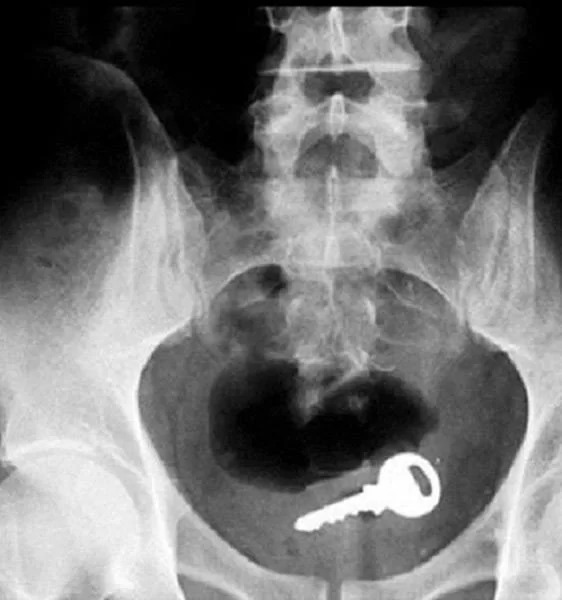

Röntgen filmlerinin tıp teknisyenleri, veteriner ve doktorlar tarafından günlük hayatta ve tedavilerde oldukça fazla kullanılıyor olmasının insanlarda bu teknoloji hakkında bilgi sahibi ve alışkanlık durumunun oluşmasına neden olduğu oldukça ortada. Yine sıradan bir gün ve rahatsızlığı sonucu hastaneye başvuran bir vatandaşın başına gelen akıl almaz olay sizlerle. Vatandaşın röntgen çekiminin ardından sonuçlarında görüntülenen görüntü bu sefer diğerlerine göre oldukça farklıydı. Görenleri şaşkına çeviren bu olay karşısında ne yapacağını bilemeyen vatandaşın hikayesi sizlerle. İşte o akıl almaz olay..

Röntgen filmlerinden akıl almaz görüntüler.. Hastane koridorlarına düşenler bilir. Doktora görün, tahlilleri yaptır, röntgenleri çektir falan filan derken sayılmadan yaşam gider. Gelin ki bu sefer o röntgen görüntülerinde nasıl ilginç şeyler çıkmış görün, ağzımız açık kaldı!

Röntgen filmlerinden çıkan akıl almaz görüntüler: